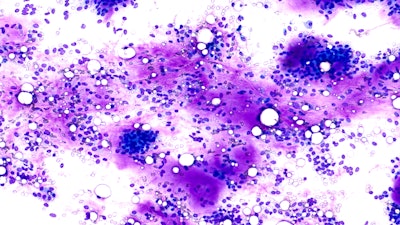

Similar to the Bethesda system for thyroid lesions, the MSRSGC includes a tiered categorical framework for reporting FNA findings of salivary gland lesions. FNAs are categorized into one of six categories: 1) nondiagnostic, 2) nonneoplastic, 3) atypia of undetermined significance (AUS), 4) neoplasm (subdivided into [a] benign neoplasms and [b] salivary gland neoplasms of uncertain malignant potential [SUMPs]), 5) suspicious for malignancy, and 6) malignant. Each category is ascribed an implied risk of malignancy (ROM) and a brief management strategy (Table 1).

Cystic salivary gland lesions also pose a challenge owing to the higher likelihood of nondiagnostic samples due to inadequate cellularity of the aspirate. For this reason, it is advised to perform a post-evacuation FNA with multiple passes for cystic salivary lesions to reduce the likelihood of a false negative result.11